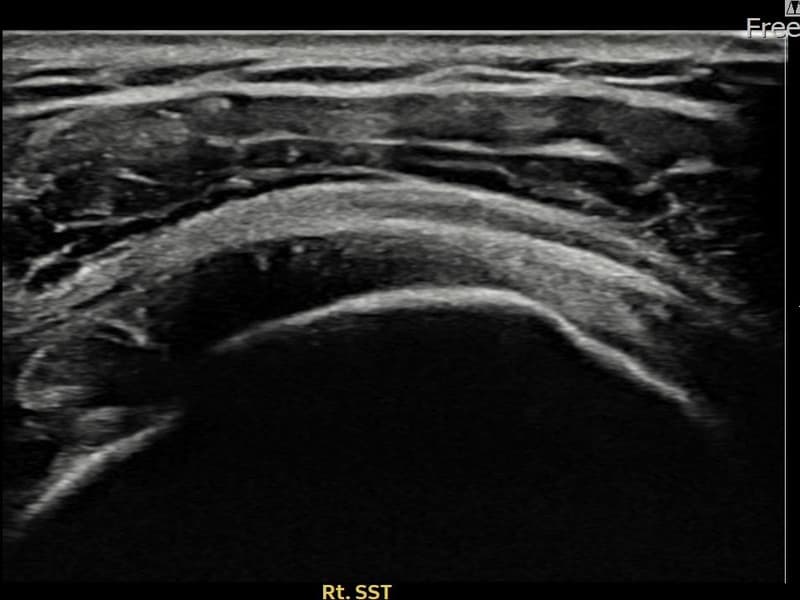

Before

시술 전 초음파 측정 결과 파열 크기는 9mm × 4mm (힘줄 두께의 약 38% 결손)로 확인되었습니다. 시술 전 초음파에서 우측 극상근건 관절면측의 에코 단절과 힘줄 내 저에코 결손 소견이 확인되었습니다. 시술 후 초음파에서 파열 부위가 재생 조직으로 채워지고 힘줄 연속성이 회복된 것이 관찰되었습니다.

50대 초반 남성 환자분으로, 우측 어깨 통증이 1년 이상 지속되었으나 바쁜 일상으로 치료를 미루시다 내원하셨습니다. 팔을 90도 이상 들어 올릴 때 통증이 심하고 야간 통증으로 옆으로 눕지 못하는 상태였습니다. 초음파 검사에서 관절면측 극상근건 부분파열이 확인되었으며, 수술 없이 초음파 유도 하 축소봉합술을 시행하였습니다. 시술 후 보조기 착용과 단계적 재활을 통해 진행하였고, 시술 13주 후 추적 초음파에서 파열 부위의 구조적 회복이 확인되어 정상 업무에 복귀하셨습니다.